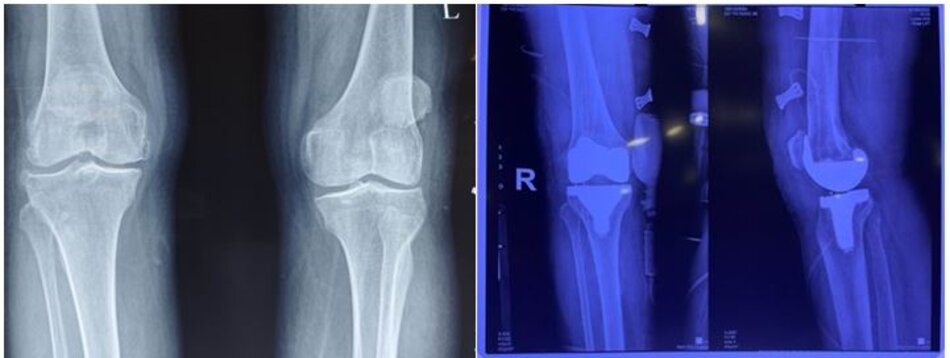

X-quang trước mổ và sau mổ bệnh nhân thay khớp gối toàn phần do thoái hoá